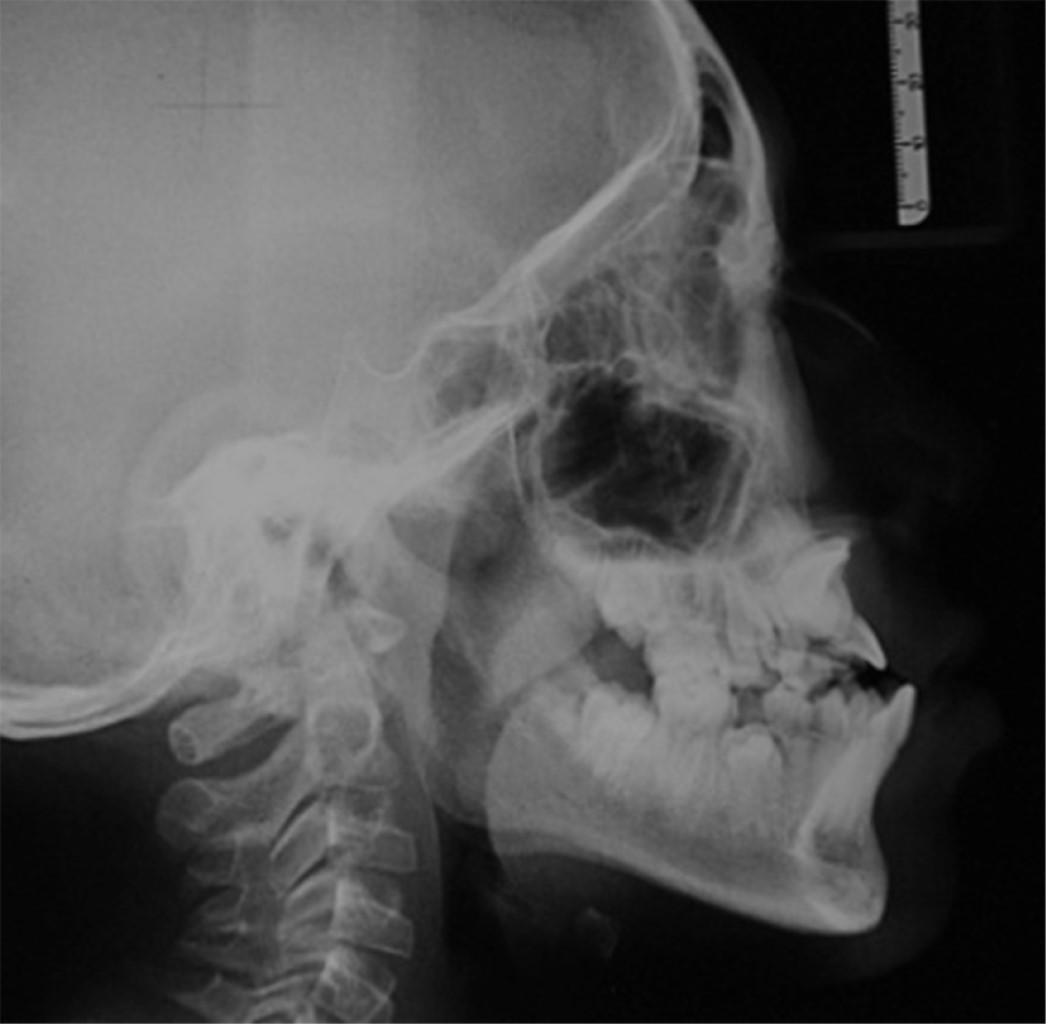

According to the extraoral and intraoral photographs (Figures 1 and 2), radiographic studies (Figures 3 and 4), and cephalometric data (Table 1), orthodontic treatment with traction of dental organs #11 and #21 was decided in order to fulfil the planned objectives. The treatment was carried out in three phases.

The duration of treatment was 48 months, the position of dental organs #11 and #21 was adequate, the overbite was corrected, bilateral class I canine and class I molar were achieved, a positive arch smile, correct anterior guidance (overjet and overbite), coincidence of midlines, elimination of open bite in the anterior sector (Figures 5 and 6); the correct position of the dental organs #11 and #21 was observed in the radiographic examination, with no root resorption and, bone neoformation adjacent to the traction site (Figure 7).

Figure 3

Figure 4